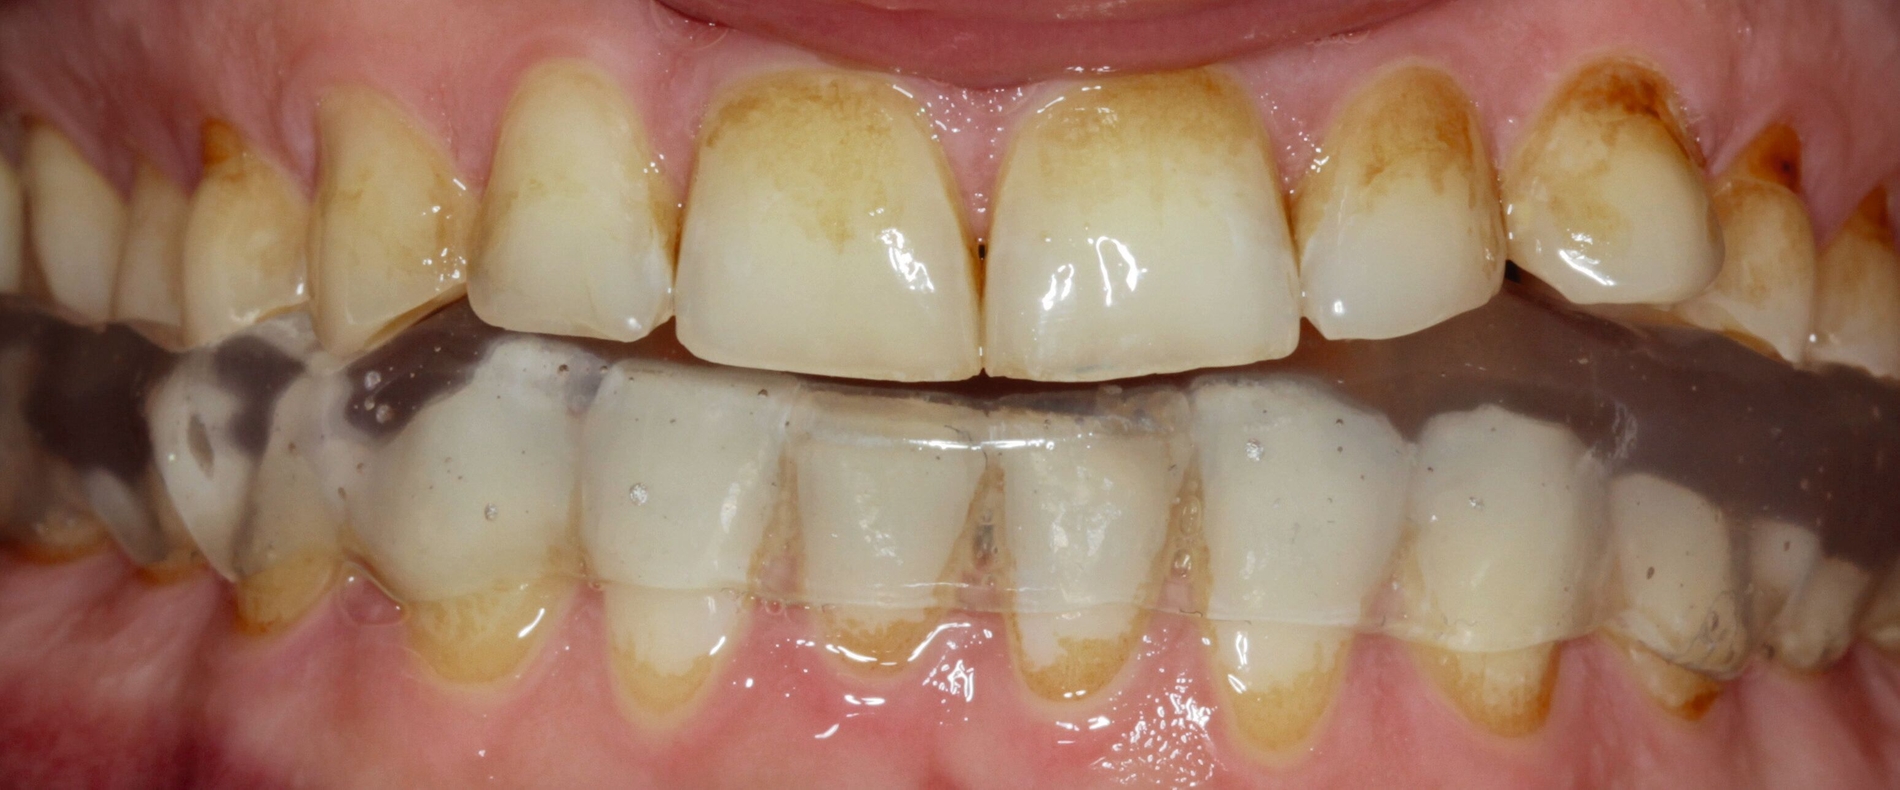

Klinisch präsentierte sich ein vollbezahntes Gebiss ohne Weisheitszähne mit Defekten an der Zahnstruktur teilweise bis ins Dentin. Es waren deutliche Erosionsspuren zu erkennen, die auf die säurehaltige Ernährung im Kurzzeitintervall zurückgeführt wurden. Der BEWE-Index war mit dem Wert 13 auffällig und kategorisierte den Schaden als ausgeprägte Erosionen. Die Zähne 14, 13 und 24 wiesen nicht-kariöse zervikale Defekte auf, diese treten häufig im Zusammenhang mit Bruxismus auf [Pecie et al., 2011]. Das CMD-Screening der Deutschen Gesellschaft für Funktionsdiagnostik und -therapie (DGFDT) [DGFDT, 2024] war unauffällig, da der Patient über keinerlei Schmerzen oder Beschwerden bei Kieferbewegungen klagte. Die manuelle Strukturanalyse (MSA) nach Bumann [Fasold und Kordaß, 2012] ergab bei diesem Patienten ein myofaziales Schmerzsyndrom. Im Prämolarenbereich imponierten Zahnhartsubstanzdefekte, die Hinweise auf starkes und häufiges Zähnepressen geben. Den Patienten selbst störten seine kälteempfindlichen Zähne sowie die Gesamtästhetik aufgrund des massiven Substanzverlustes.

Therapie

Zu Beginn wurden mit Alginat Abformungen der Ausgangslage genommen. Anhand der Situationsmodelle konnten mithilfe einer Modellanalyse nach dem Udo-Plaster-Protokoll [Plaster und Köttgen, 2020] Rückschlüsse auf einen vertikalen Höhenverlust von etwa 3 - 4 mm gezogen werden. Für die Registrierung der neuen Höhe wurde der Patient mit einer temporären Einweg-Schiene (Aqualizer®, MediPlus GmbH, Unterleinleiter) deprogrammiert. Anschließend wurde am stehenden Patienten ein Bis-Acrylat-basierter Frontzahn-Jig (LuxaBite, DMG, Hamburg) angefertigt, so dass die Bissnahme als vorläufige patientenindividuelle Myozentrikposition reproduzierbar im Seitenzahnbereich mit einem A-Silikon (Kanibite hart, Kaniedenta, Herford) erfolgen konnte. Basierend auf dieser Höhe wurde eine Bisserhöhungsschiene angefertigt, die der Patient über sechs Monate lang trug. Nach einem Intraoralscan des Ober- und Unterkiefers (Primescan, Dentsply Sirona, Bensheim) konnte ein digitales Wax-up erstellt werden. Auf den 3-D-gedruckten Wax-up-Modellen wurde ein Silikonschlüssel für die Mock-up-Versorgung hergestellt und mit einem Bis-Acrylat-Komposit (Luxatemp Star, DMG, Hamburg) umgesetzt.

Da der Patient mit der Situation zufrieden war, konnte nach einigen Wochen die endgültige Versorgung bestehend aus Lithiumdisilikat-Kronen (e.max®, Ivoclar, Schaan, Liechtenstein) adhäsiv mit einem dualhärtenden Befestigungskomposit (RelyXUltimate™, 3M™, Neuss) eingesetzt werden. Der Patient bekam außerdem eine Unterkiefer-Aufbissschiene mit adjustierter Kaufläche für die Nacht.